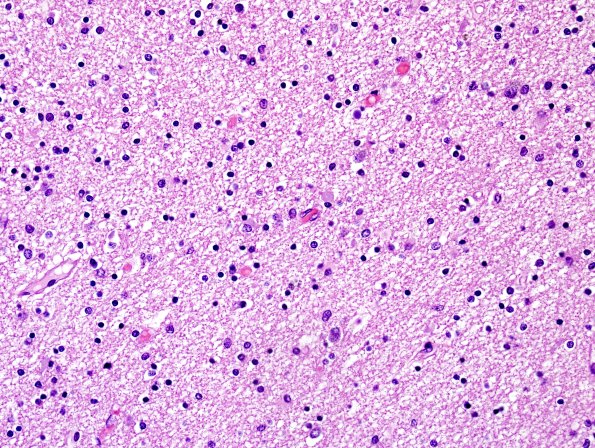

Washington University Experience | NEURODEGENERATION | Globular Glial Tauopathy (GGT) | 1D1 Globular Glial Tauopathy (Case 1) L23 Entorhinal WM H&E 4.jpg

1D1-4 This is entorhinal cortex white matter which has a lesser degree of involvement by GGI than cingulate. There is variation in size and shape in GGI in the case, not all are precisely globular. (H&E)